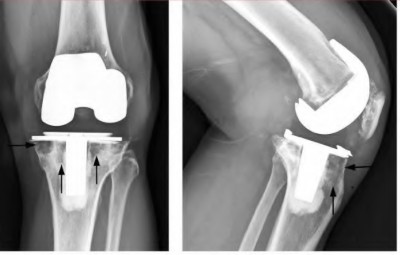

A 64-year-old woman with osteoarthritis underwent bilateral total knee replacement 3 years ago. Current radiographs are shown in Figure A. She reports a 3-month history of bilateral knee pain while at rest and increasing swelling in the knees. Her ESR and CRP are elevated and bilateral knee aspiration cultures reveal Staphylococcus aureus. What is the most likely outcome if the patient undergoes simultaneous, bilateral knee resection arthroplasty with cement spacer and a course of intravenous antibiotics?

This patient presents with bilateral total knee arthroplasty infection.

Wolff et al report Level 4 evidence of 18 patients followed an average of 5 years after bilateral TKA infection. Eleven patients were initially treated with attempts to salvage the original prosthesis (polyethylene l liner exchange, I&D, IV antibiotics and chronic oral suppressive antibiotics. With prosthesis retention, 9/11 (81%) developed recurrent infection at a mean of 15 months. The other 10 patients initially underwent resection arthroplasty with cement spacer and a course of IV antibiotics. Seven of the 10 (70%) underwent reimplantation at a mean of 3 months (6 weeks to 5 months) and none of the patients required revision at mean of two years follow up. Satisfaction rates were significantly higher among this group of patients. The authors advocate the protocol of bilateral TKA resection arthroplasty with cement antibiotic spacer and course of IV antibiotics followed by prosthesis reimplantation.